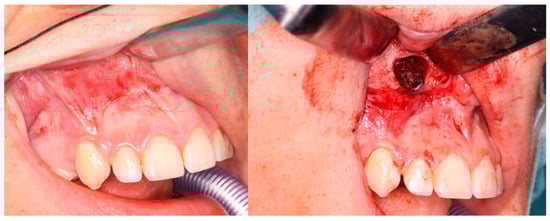

3. Results

3.2. Injections

4. Discussion